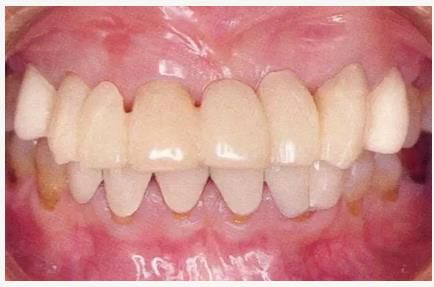

圖6-4,5

左上2,3和右上1,3存在齦下齲壞,但牙齒周圍有充足的角化齦。左上4和右上4頰側(cè)的角化齦較少。

圖6-6~8

左上3到右上3的牙齒,通過包含牙槽骨外科處理在內(nèi)的APF進(jìn)行治療,確保了獲得biologic width所必需的、3mm以上的健全牙體組織。為獲得附著齦,使用FGG對左上4和右上4的牙齒進(jìn)行了治療。

圖6-9 牙周外科治療5個月后,最終取模前的狀態(tài)?;乐車@得了充足的附著齦。